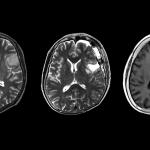

6. Какви са съвременните диагностични методи за мозъчни тумори?

Най-важната роля има лекарят: да слуша внимателно пациента и да прецени правилно конкретната ситуация. След това извършваме общ и неврологичен преглед, за да проверим за симптоми на заболяването. Прилагаме образни диагностични методи, сред които най-важен е магнитният резонанс. Това ни осигурява голям обем от информация за местоположението и вида на лезиите. Тази информация е от ключово значение за решението какво лечение да се приложи върху мозъчния тумор, защото всеки случай има своите особености.

Технологиите са много важни за нас: използваме ги при диагностицирането, по време на операция, но също и при прилагането на някои терапии. При поставянето на диагнозата разчитаме на напреднали технологии като ядрено-магнитен резонанс (ЯМР), с изключително усъвършенствани програми за диагностициране. По време на операции прибягваме към технологии като интраоперативен ЯМР, ултрасонография, ендоскопия и микроскопи, които ни позволяват да постигнем високо ниво на визуализация, или невронавигация за насочване вътре в мозъка. Използваме всички тези технологии, за да повишим безопасността е успеваемостта при хирургични интервенции.